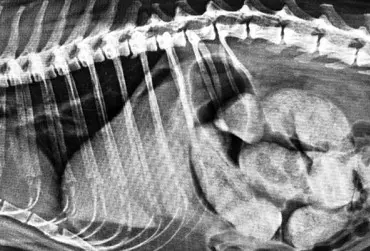

W praktyce weterynaryjnej jest wiele metod diagnostycznych stosowanych w chorobach przewodu pokarmowego. Takie badania jak ultrasonografia, radiografia, endoskopia, tomografia komputerowa, rezonans magnetyczny rozszerzają możliwości diagnostyczne w zrozumieniu chorób jamy brzusznej. Niektórzy pacjenci – poza badaniem klinicznym, wywiadem i badaniem krwi – przechodzą szerszą diagnostykę. Mogą mieć wykonane pojedyncze lub wielokrotne badania obrazowe. Ultrasonografia jest najbardziej popularną metodą diagnostyczną, opiera się na wysokich częstotliwościach ultradźwięków generowanych przez sondę, która poprzez komputer uwidacznia obraz naczyń krwionośnych, tkanek i narządów. Zdjęcie rentgenowskie jamy brzusznej to również typowa procedura medyczna, która pozwala na uwidocznienie kształtów i lokalizacji tkanek, narządów w jamie brzusznej. Główne zastosowanie radiografii to także choroby kości, stawów oraz diagnostyka zmian w klatce piersiowej.